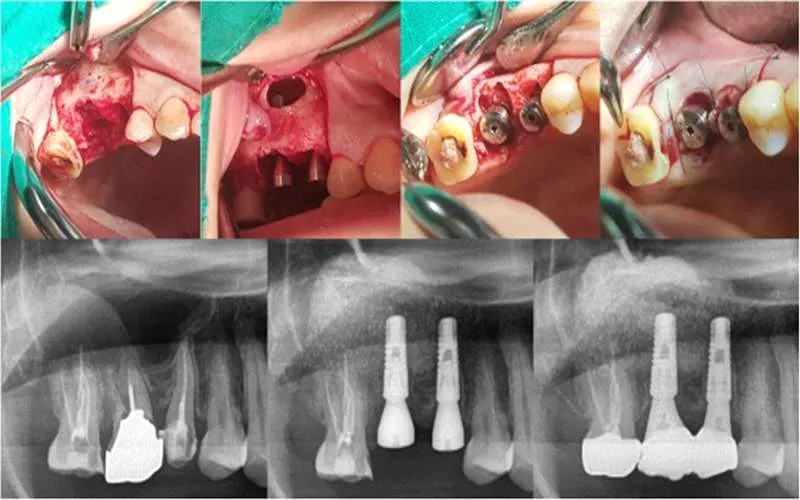

در طی این جراحی

| 1 | قسمتی از لثه در بخش جانبی فک بالا بریده شده و روی استخوان سوراخی ایجاد می شود |

| 2 | سپس، از طریق این سوراخ، دندانپزشک مخاطی را پیدا می کند که سینوس داخل آن را می پوشاند |

به این غشاء، اشنایدر هم می گویند.

سپس

| 3 | دندانپزشک می تواند با ابزارهای مخصوص جراحی و با رعایت احتیاط بدون آسیب به غشاء، مخاط سینوس را بلند کرده و مواد استخوانی را در آنجا می ریزد |

| 4 | بعد از اینکه عمل لیفت سینوس باز تمام شد، زخم ها بخیه زده می شوند |

به منظور تشکیل بافت استخوانی به صورت کامل باید بازه زمانی 4 تا 6 ماه منتظر ماند. پس از گذشت این بازه زمانی دندانپزشک می توانند اقدام به نصب ایمپلنت کند.